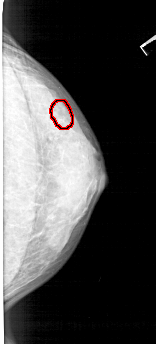

A_1352_1.RIGHT_MLO

RIGHT_MLO LINES 5161 PIXELS_PER_LINE 2146 BITS_PER_PIXEL 12 RESOLUTION 43.5 OVERLAY

FILE: A_1352_1.RIGHT_MLO.OVERLAY

TOTAL_ABNORMALITIES 1

ABNORMALITY 1

LESION_TYPE CALCIFICATION TYPE PLEOMORPHIC DISTRIBUTION CLUSTERED

ASSESSMENT 4

SUBTLETY 2

PATHOLOGY BENIGN

TOTAL_OUTLINES 1

BOUNDARY